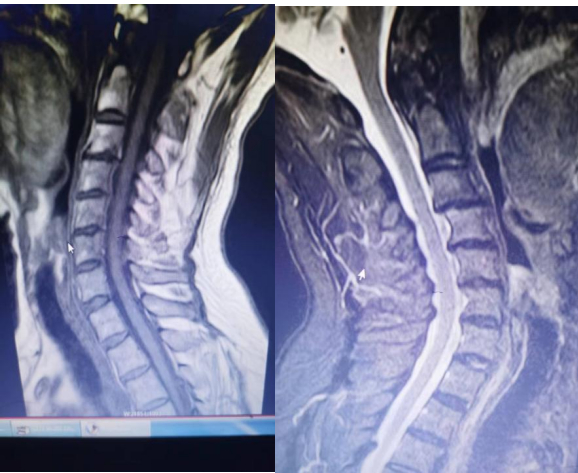

随立即行颈椎磁共振检查,结果如下:

至此诊断明确:颈性心绞痛。

常规颈椎磁共振成像(MRI)检查已被推荐用于颈椎心绞痛的功能评估。MRI可以显示颈椎的退行性改变,包括椎间盘突出、脊髓受压或脊索侵犯[1]。MRI的应用使得我们得以发现更为罕见的颈性心绞痛,例如脊髓梗死导致的心绞痛[3]、寰枢椎不稳定导致的心绞痛[4]